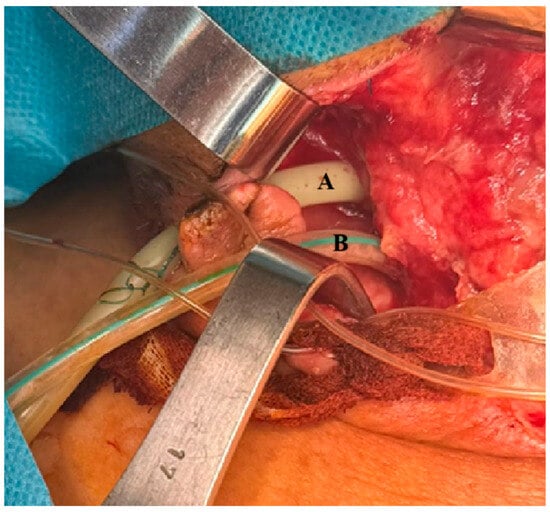

Adaptation of Endoluminal Vacuum Therapy via Extra-Luminal Access in the Treatment of a High Pharyngeal Fistula: Technical Feasibility and Outcome

Bogdan-Mihnea Ciuntu, Daniel Vasile Timofte, Andreea Ludușanu, Mihaela Corlade-Andrei, Roxana Elena Ciuntu, Irina Mihaela Abdulan, Alexandra-Simona Zamfir, Adelina Tanevski, Mădălina Maxim, Gheorghe Balan, Anca Bordianu and Bogdan Cobzeanu

Life 2025, 15(11), 1660; https://doi.org/10.3390/life15111660 - 23 Oct 2025

Background: Perforation of the piriform sinus is a rare but severe clinical event that can lead to cervico-thoracic mediastinitis, a life-threatening condition requiring urgent multidisciplinary intervention. Among its etiologies, accidental ingestion of foreign bodies, including dental prostheses, is uncommon but poses significant risks due to the anatomical vulnerability of the hypopharyngeal structures. Methods: We report a rare case of right piriform sinus perforation secondary to the ingestion of a dental prosthesis, complicated by cervico-mediastinitis, sepsis, tracheostomy, and sacral pressure ulcer. The clinical course required emergency surgical intervention and intensive supportive care. Results: A novel aspect of this case was the use of the Endoscopic Vacuum-Assisted Closure (EVAC) irrigation system as an adjunctive technique in the management of deep cervical drainage. Rather than approaching the fistula from within the lumen, the team created a controlled external drainage system, adaptation of the vacuum-assisted closure therapy directly over the fistulous tract. Conclusions: This case highlights the importance of early diagnosis, high clinical suspicion and coordinated management in the treatment of piriform sinus perforations. It also illustrates the potential applicability of modern technologies such as negative pressure irrigation in the complex management of deep neck infections and mediastinitis.